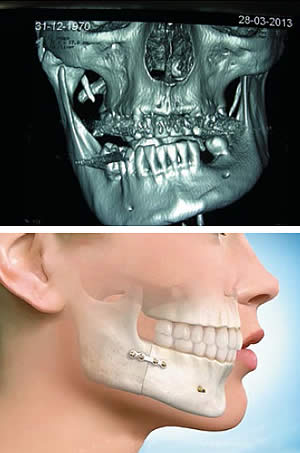

Kraniomaksilofacijalna hirurgija bavi se i anomalijama vilica i kostiju lica, urođenim i stečenim. Stečene anomalije mogu biti posledica infekcije zgloba, ali neretko nastaju pri porođaju, kad se novorođenče povredi forceps klještima. Posledica takvih povreda lica bebe može biti zastoj u razvoju povređene strane lica pa se, obično između šeste i osme godine života deteta, oštećeni vilični zglob odstranjuje i na njegovo mesto ugrađuje deo rebra pacijenta sa hrskavicom. Ovakav kompozitni autotransplant nastavlja da raste na mestu spoja rebarne kosti i hrskavice, gde je inače centar rasta, čime se sprečava asimetrija lica. U slučaju da je ovakav zahvat iz bilo kog razloga propušten, čeka se pubertet, odnosno navršena 16. godina života kod devojaka, ili 18. kod mladića, da se primeni složen rekonstrukcioni zahvat, zamena nekog zgloba, i sl.

1.Pacijent sa ankilozom viličnog zgloba kao posledica porođajne traume zbog primene tzv. forceps klešta u toku izvlačenja bebe. Centar rasta donje vilice oštećen je kleštima, zglob je srastao u koštanu masu a donja vilica se nije razvijala.

2.Isti pacijent, 14 godina posle operacije. Zglob je zamenjen rebrom sa hrskavicom a donja i gornja vilica su operisane sa ciljem da se uspostave harmoničan izgled lica i funkcija otvaranja usta i žvakanja. |